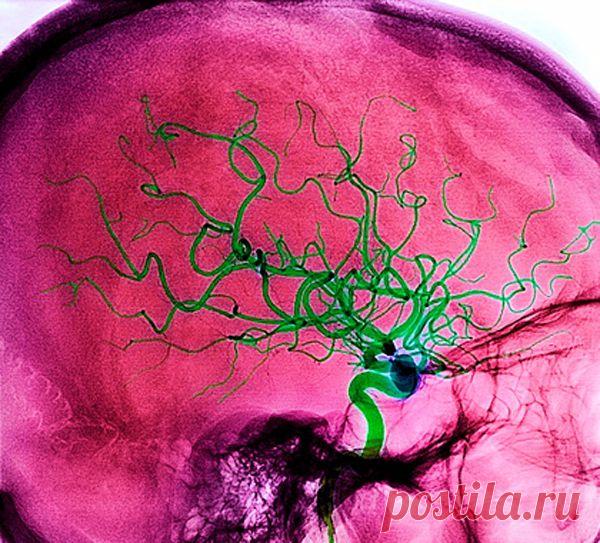

Почему возникает инсульт и как этого избежать..